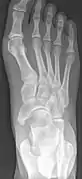

Radiological images

Type 2